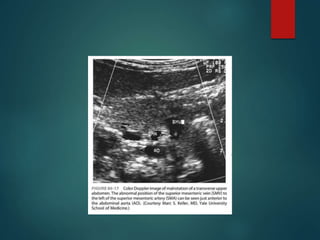

Ultrasound • Reversal ofthe normal anatomic relationship between the SMA and • “whirlpool sign” - midgut volvulus.